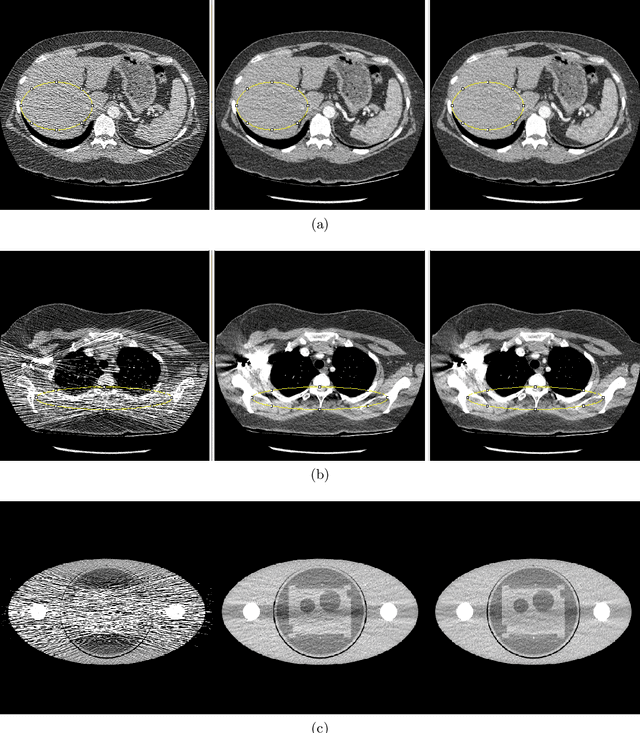

Abstract:In computed tomographic imaging, model based iterative reconstruction methods have generally shown better image quality than the more traditional, faster filtered backprojection technique. The cost we have to pay is that MBIR is computationally expensive. In this work we train a 2.5D deep learning (DL) network to mimic MBIR quality image. The network is realized by a modified Unet, and trained using clinical FBP and MBIR image pairs. We achieve the quality of MBIR images faster and with a much smaller computation cost. Visually and in terms of noise power spectrum (NPS), DL-MBIR images have texture similar to that of MBIR, with reduced noise power. Image profile plots, NPS plots, standard deviation, etc. suggest that the DL-MBIR images result from a successful emulation of an MBIR operator.

Abstract:Low x-ray dose is desirable in x-ray computed tomographic (CT) imaging due to health concerns. But low dose comes with a cost of low signal artifacts such as streaks and low frequency bias in the reconstruction. As a result, low signal correction is needed to help reduce artifacts while retaining relevant anatomical structures. Low signal can be encountered in cases where sufficient number of photons do not reach the detector to have confidence in the recorded data. % NOTE: SNR is ratio of powers, not std. dev. X-ray photons, assumed to have Poisson distribution, have signal to noise ratio proportional to the dose, with poorer SNR in low signal areas. Electronic noise added by the data acquisition system further reduces the signal quality. In this paper we will demonstrate a technique to combat low signal artifacts through adaptive filtration. It entails statistics-based filtering on the uncorrected data, correcting the lower signal areas more aggressively than the high signal ones. We look at local averages to decide how aggressive the filtering should be, and local standard deviation to decide how much detail preservation to apply. Implementation consists of a pre-correction step i.e. local linear minimum mean-squared error correction, followed by a variance stabilizing transform, and finally adaptive bilateral filtering. The coefficients of the bilateral filter are computed using local statistics. Results show that improvements were made in terms of low frequency bias, streaks, local average and standard deviation, modulation transfer function and noise power spectrum.

Abstract:Deep learning (DL) shows promise of advantages over conventional signal processing techniques in a variety of imaging applications. The networks' being trained from examples of data rather than explicitly designed allows them to learn signal and noise characteristics to most effectively construct a mapping from corrupted data to higher quality representations. In inverse problems, one has options of applying DL in the domain of the originally captured data, in the transformed domain of the desired final representation, or both. X-ray computed tomography (CT), one of the most valuable tools in medical diagnostics, is already being improved by DL methods. Whether for removal of common quantum noise resulting from the Poisson-distributed photon counts, or for reduction of the ill effects of metal implants on image quality, researchers have begun employing DL widely in CT. The selection of training data is driven quite directly by the corruption on which the focus lies. However, the way in which differences between the target signal and measured data is penalized in training generally follows conventional, pointwise loss functions. This work introduces a creative technique for favoring reconstruction characteristics that are not well described by norms such as mean-squared or mean-absolute error. Particularly in a field such as X-ray CT, where radiologists' subjective preferences in image characteristics are key to acceptance, it may be desirable to penalize differences in DL more creatively. This penalty may be applied in the data domain, here the CT sinogram, or in the reconstructed image. We design loss functions for both shaping and selectively preserving frequency content of the signal.